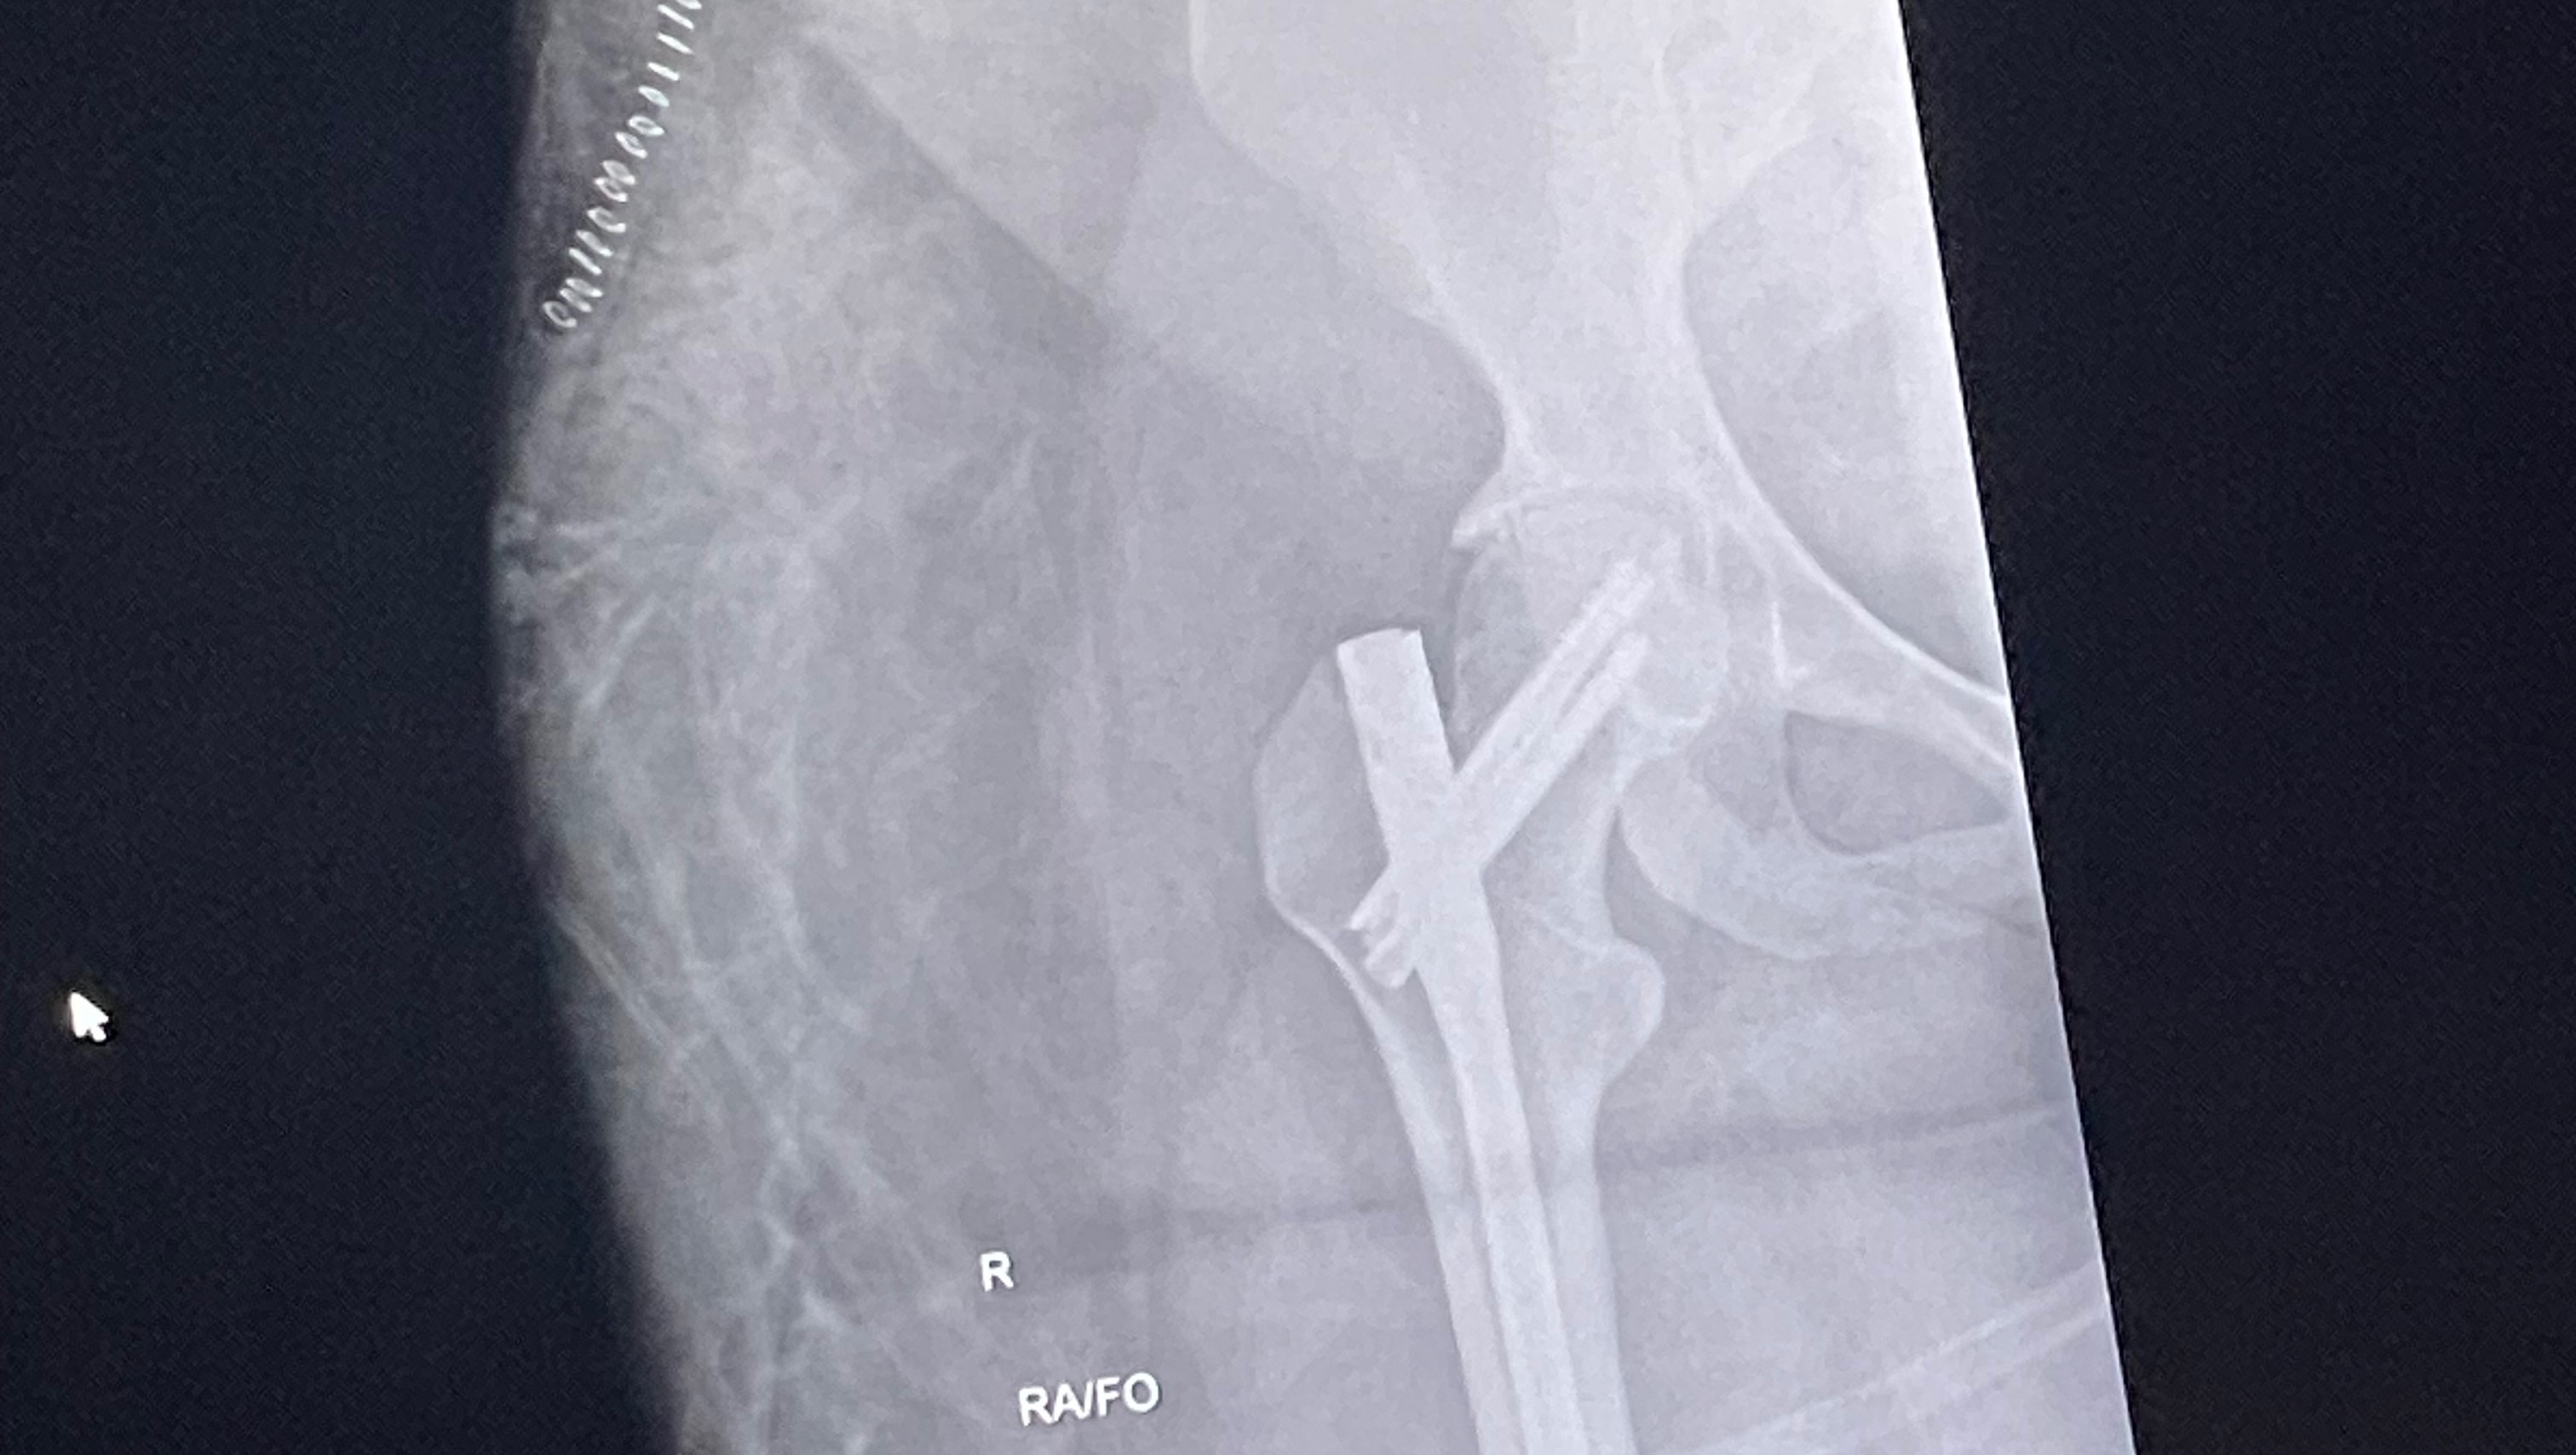

Hi, my name is Nesha Paige , and I’m a dedicated esthetician with a passion for helping others feel confident and beautiful in their own skin. Unfortunately, life took an unexpected turn when I was involved in a serious head-on collision car accident. While I’m grateful to be alive, the aftermath has left me with overwhelming financial challenges.

Due to my injuries, I’ve been unable to work, and the mounting medical bills, therapy costs, and loss of income have taken a significant toll. As an esthetician, my hands are my livelihood, and I’m now working hard to recover so I can return to doing what I love—helping my clients look and feel their best.